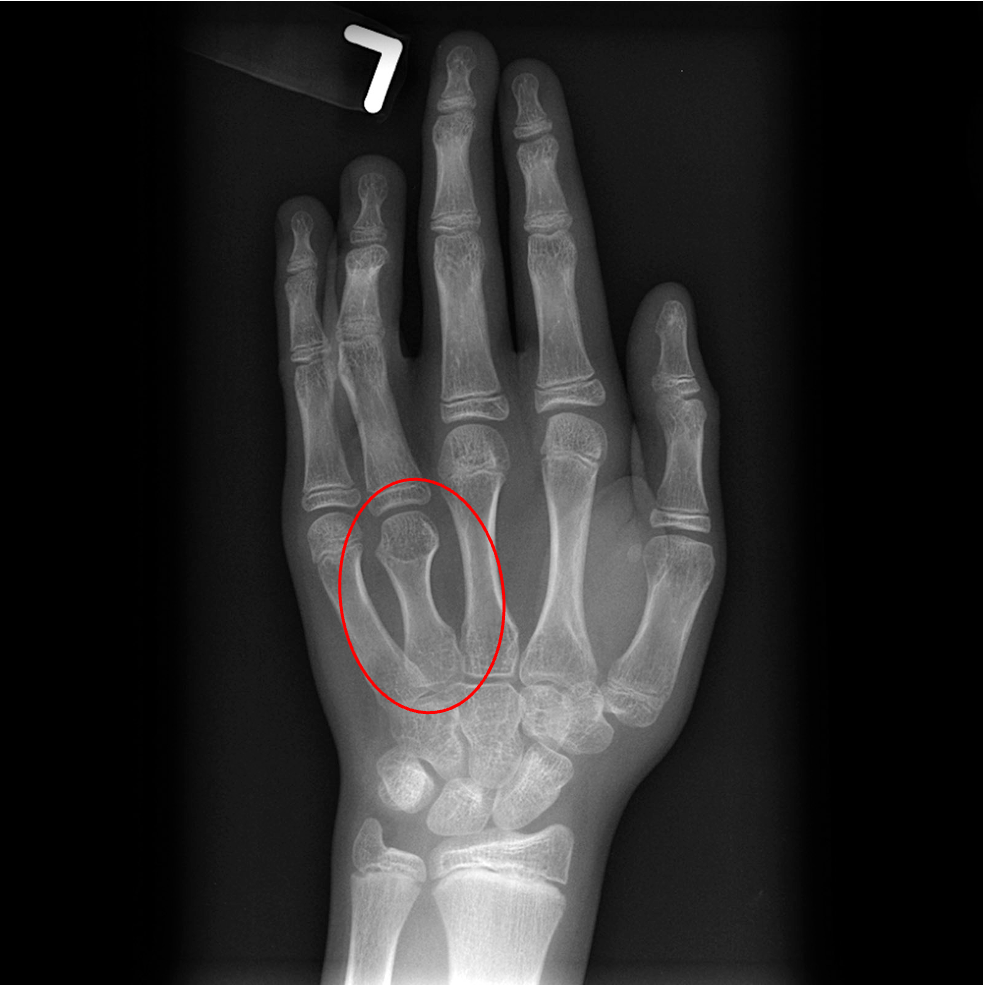

Img | Wrist radiograph: Short 4th metacarpal bone |

• 신체 진찰에서 넓은 유두 사이 거리, 방패형 가슴, 짧은 목과 같은 체형 이상이 관찰되고, 뼈 나이 평가를 위해 촬영한 손 X선에서 4번째 중수골 단축(short 4th metacarpal)이 확인되는데, 이는 터너 증후군을 시사하는 특징적인 소견이다.

• 참고로 제시된 손목 X선 사진에서 뼈나이는 13세 정도로 평가되는데, 터너 증후군에서는 뼈나이가 실제 연령과 비슷하거나 에스트로겐 결핍으로 인해 약간 지연될 수 있다.